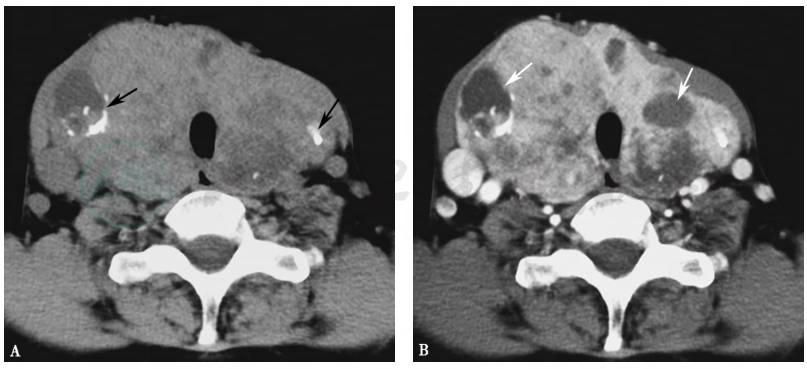

图2多结节性甲状腺肿CT表现

A.CT平扫双侧甲状腺不规则增大,内见多发结节,伴有囊变和钙化(黑色箭头);B.增强扫描多发结节更清楚,大小不一,囊变区无强化(白色箭头)